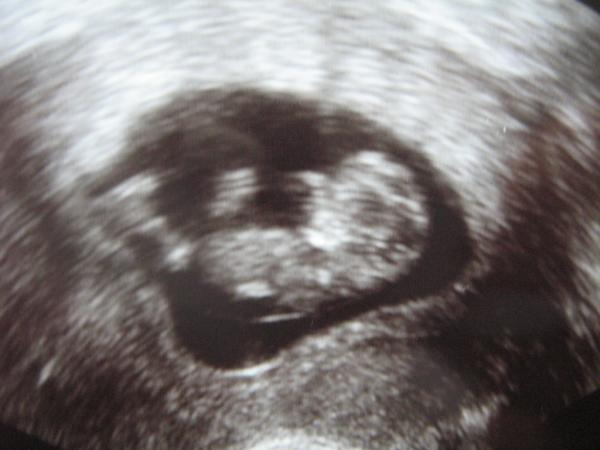

Hatte ja heute meinen FA Termin und es ist alles in bester Ordnung. Das Baby ist schon stolze 4 cm groß. Ich bin immer noch total überwältigt, wie schnell es gewachsen ist. Vor 4 Wochen war nur ein kleines etwas zu sehen und heute sehe ich meinen kleinen Wurm in ganzer Pracht!!! Hänge euch mal 2 US Bilder mit dran, eins von der 7. SSW und eins aus der 11. SSW. Viele liebe Grüße, Peach